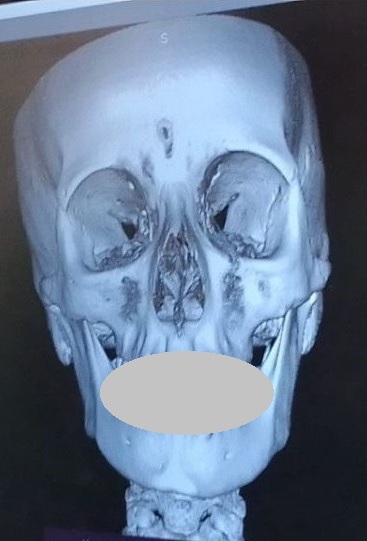

Non prendiamo come riferimento l’immagine di profilo più copiata nel mondo della postura e di certe discipline mediche come l’odontoiatria, la gnatologia e l’osteopatia; prendiamo l’immagine della scoperta OcclusioneGravità® che indica un teschio con rapporto scheletrico a-simmetrico:

Che questo rapporto tra cranio e mandibola non è una condizione patologica ma è la condizione ABITUALE, NORMALE per tutta la popolazione mondiale.

La variabile che rende ogni individuo diverso dall’altro è la differenza tra i gradi di Dis-Equilibrio tra queste parti scheletriche (e conseguentemente articolari e muscolari) e la loro disposizione sui TRE assi spaziali (frontale, longitudinale, sagittale).

Questa è la vista frontale.

Per ragioni di praticità dobbiamo utilizzare un rapporto scheletrico molto evidente come questo:

Il rapporto scheletrico è molto simile all’immagine creata da Formia Maurizio e pubblicata nel suo libro nel 2009, copiata senza citarla in numerosi documenti e riviste scientifiche.

Abbiamo coperto volutamente e provocatoriamente i denti perchè lo scheletro si vede ugualmente non simmetrico anche senza bocca e denti. Si vede anche senza una lastra: